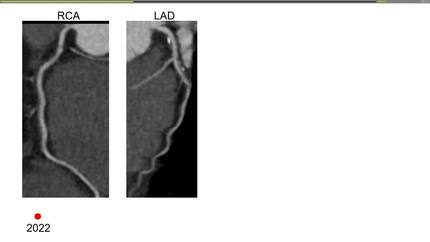

Case 2: a 55-year-old woman, borderline 10-year ASCVD risk, hesitant about lifelong statins.